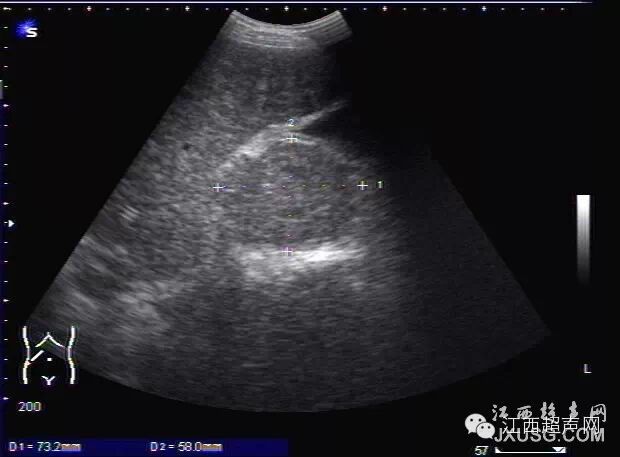

2.一些自觉腹部有包块的患者,新手会把正常椎体结构误诊为腹膜后占位性病变。